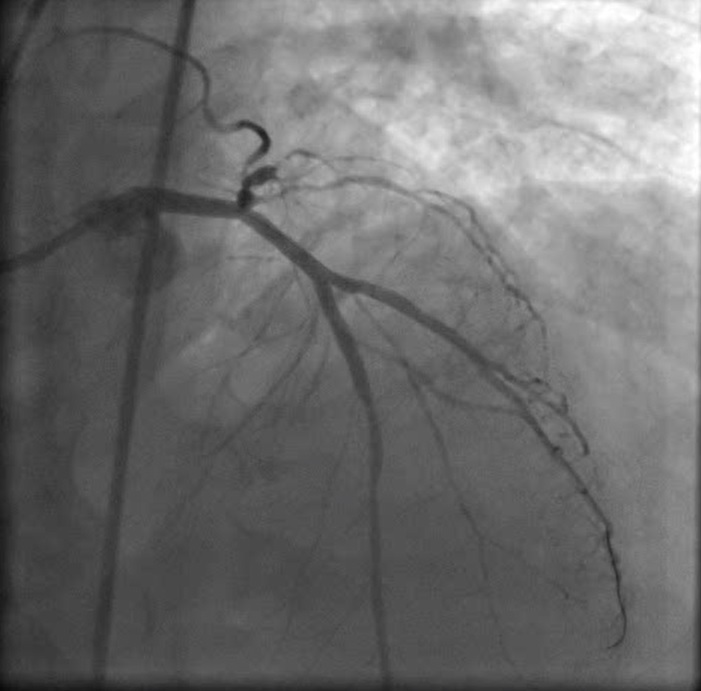

- Koroner Anjiografi ve Balon/Stent İşlemi

- Kronik Tam Tıkalı Kalp Damarında Balon/Stent İşlemi

- Ana Dal ile Birlikte Yan Dal(lar)ı da Tutan Çatal Lezyonlarda (daralma) Balon/Stent İşlemi